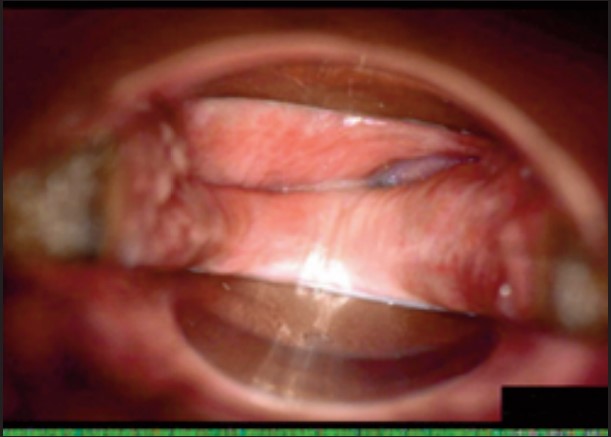

У пацієнток 1, 2 і 3 вагінальні складки утворилися та увиразнилися помітніше та сильніше, ніж вони були до лікування, ми оцінили цей клінічний результат після 1-го сеансу (через 16 діб). На нашу думку, такі виразні складки свідчать про підтяжку слизової оболонки піхви, що добре впливає на ущільнення піхви та проблему нетримання сечі. Через 36 діб після процедури ми спостерігали, що зруйнована анатомічна структура піхви відновила Н-подібну форму, тобто стала набагато здоровішою. Зокрема, у пацієнтки 4 структура піхви була цілковито зруйнована, стінки піхви обвисали через втрату еластичності. Однак через 36 днів після процедури структура піхви повністю відновила здорову Н-подібну форму [Див. Малюнок 3].

Пацієнтка №3

До

Після 16 діб

Після 36 діб

| Вік | 46 |

| Пологи | Природні. 2 хлопчики. |

| Лікування | 2 сеанси / 1 місяць |

| Огляд | 16, 36 діб |

| Протокол | 1 сеанс – 440 імпульсів 2 сеанс – 200 імпульсів |

| Результати | √ Відновлено H-подібну структуру √ Дещо зменшилися симптоми SUI √ Зросло задовлення партнера √ Зросло задоволення пацієнтки |